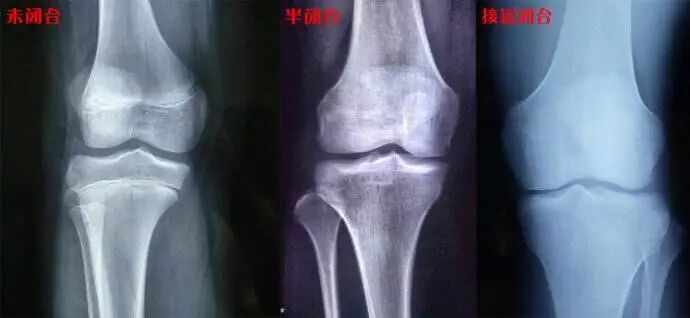

先放结论!宾夕法尼亚的教授就曾发表过一篇论文,指出:在骨骺线闭合前,阻力训练并不会对身高造成影响。

我自杠:你确定百分百不会?万一阻力训练让骨骺线提前闭合呢?

确实有这个风险,不科学的阻力训练会导致受伤,伤到骨头啥的,有可能会导致骨骺线提前闭合。

所以综合看来,合理不易受伤的计划和适中的重量不会对孩子的身高有影响。